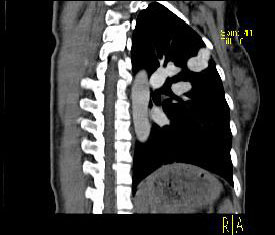

男性,26岁,头晕、气逼三年余,CT检查如图所示,请选择的最可能诊断 ( ) XN-27051.jpg XN-27052.jpg XN-27053.jpg XN-27054.jpg

题型: 单选题 分类: 心血管内科

• D.动静脉畸形